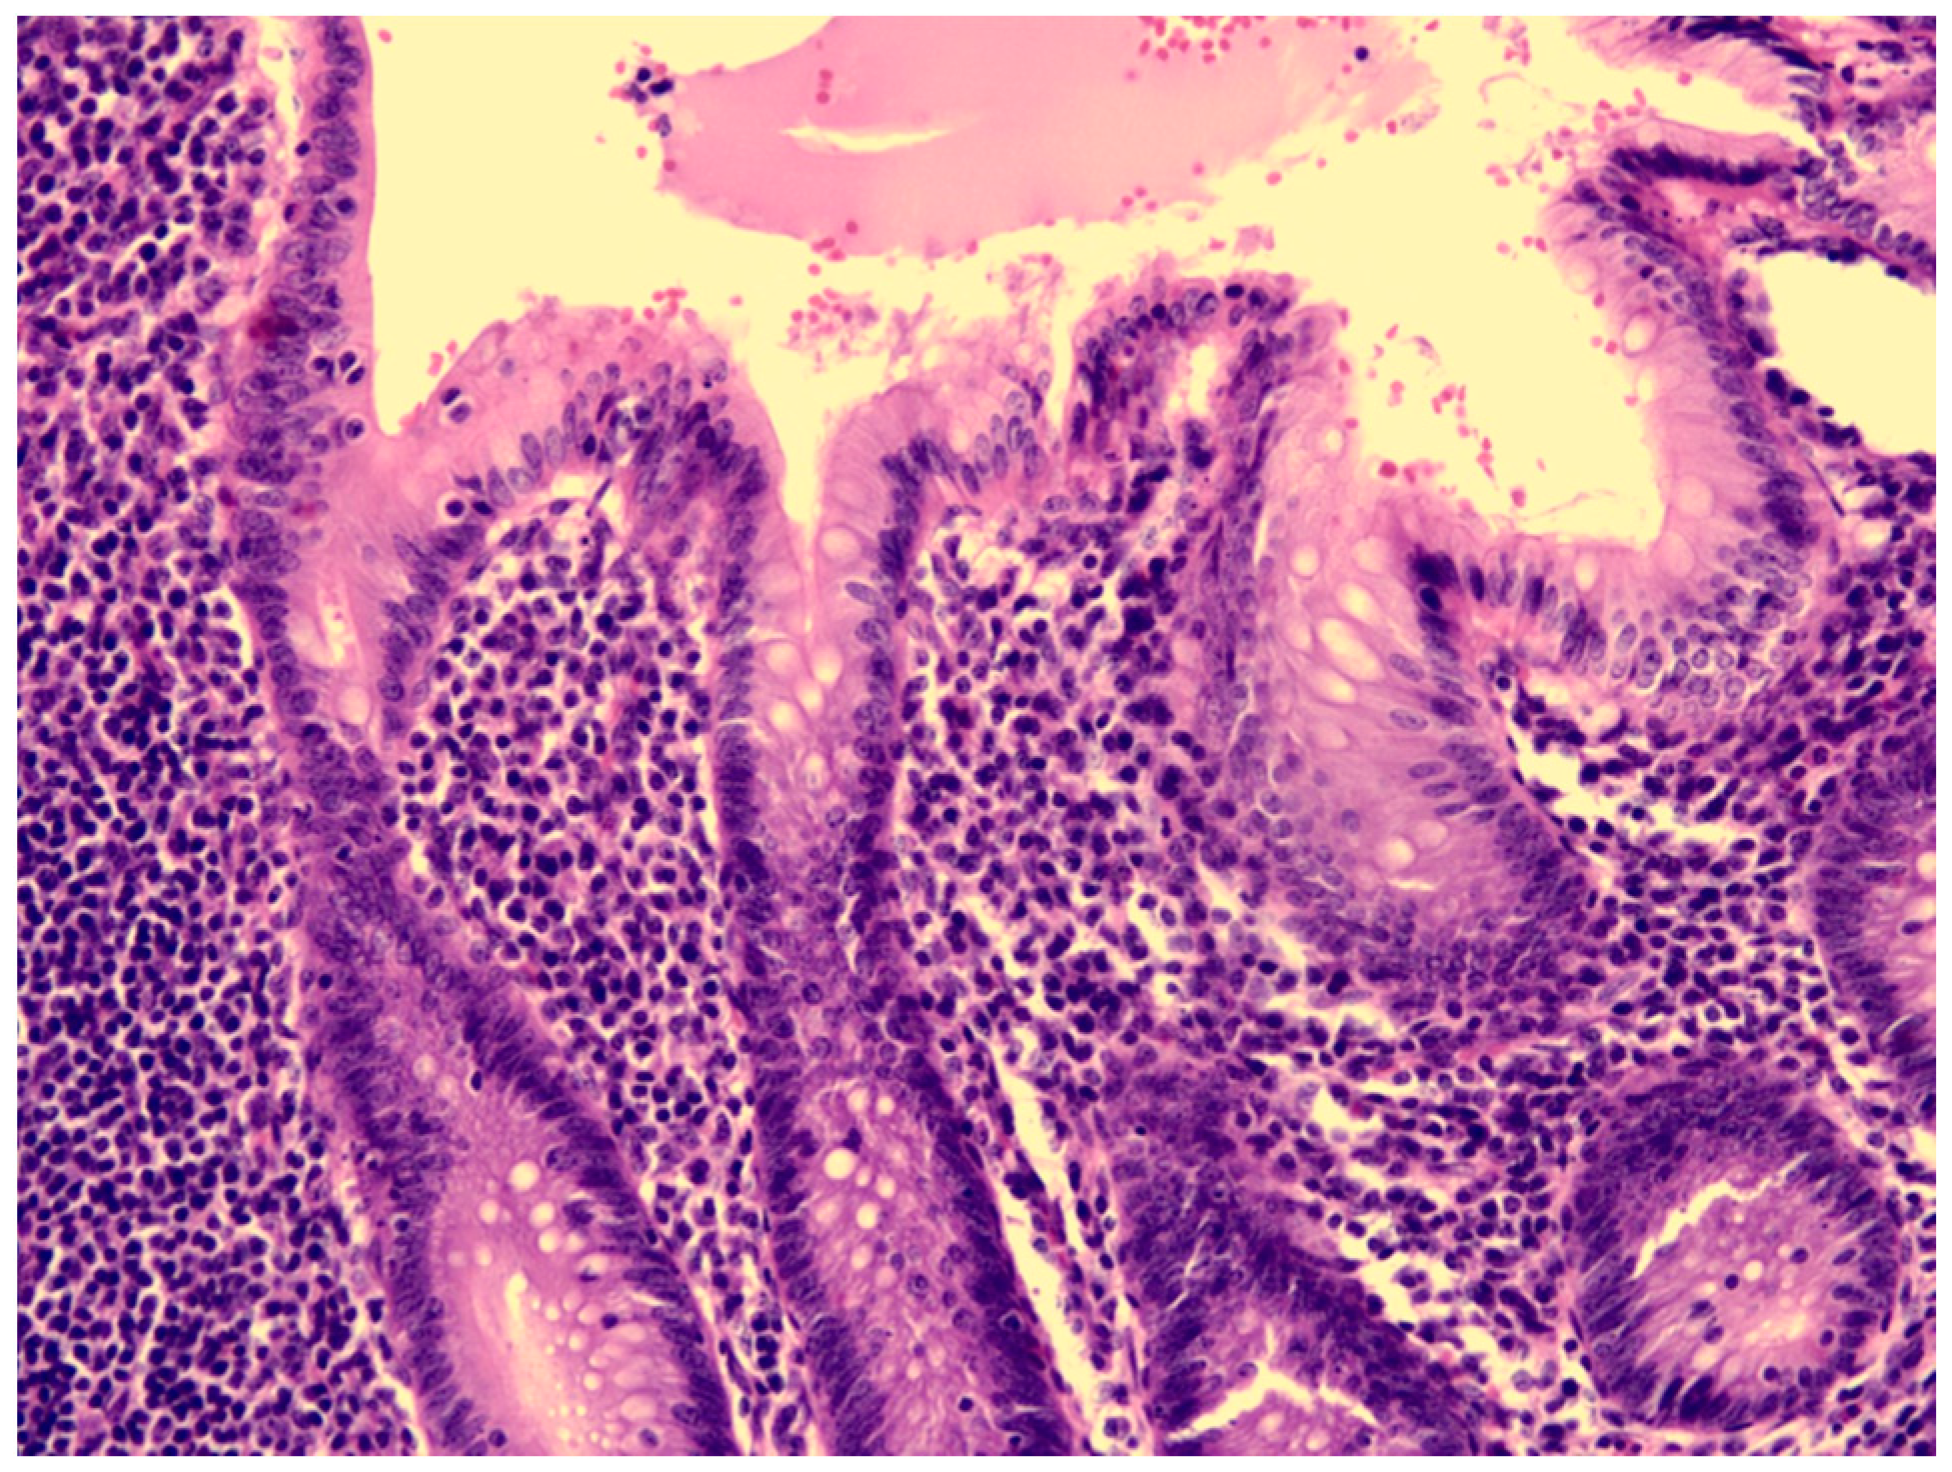

| Our patient | Yes | Hyperemic and engorged appendix with fibrin coating | Yes | Complete KD |